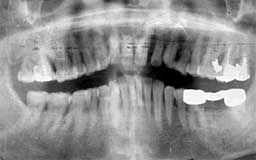

★ T君 15歳

次に登場していただくT君は、主訴の治療が終わっても他の歯も治して帰る普通のタイプ

です。日本人のほとんどがこのパターンではないでしょうか。15歳でお見えになったときに

はやむなく抜髄した歯が4本で、それ以外にも抜髄寸前みたいな歯が数本ありました。20年前

ですから強引なメインテナンスの誘いはしませんでしたが、その後2〜3年毎に何か不都合が

生じて治療を繰り返してきました。

途中ほんの1回か2回メインテナンスを続けたこともありましたが、どうしても理解して

もらえないまま20年が経過してしまいました。20年後の現在、過去に行った根の治療に根尖

病巣ができたために再治療を行っている最中です。幸いにも抜歯しなくてはならない歯はあ

りませんが、11本も神経を抜いた景観は見事なものです。

| T君 初診時 15歳 男性 抜髄した歯は1本もないが、初診時に抜髄した歯が4本 |

T君 20年後 34歳 メインテナンスの必然性を何度も説明したが理解されず、何か不都合が生じたときに来院し そのたびに主訴である歯は抜髄を繰り返す |